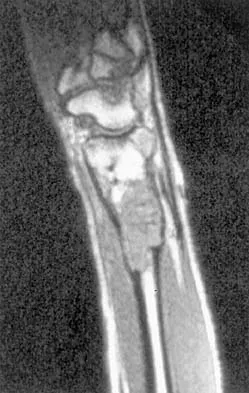

Figures 27a through 27c show the AP radiograph, MRI scan, and biopsy specimen of an otherwise healthy man who has a painful wrist. Serum chemistry studies are normal. What is the most likely diagnosis?